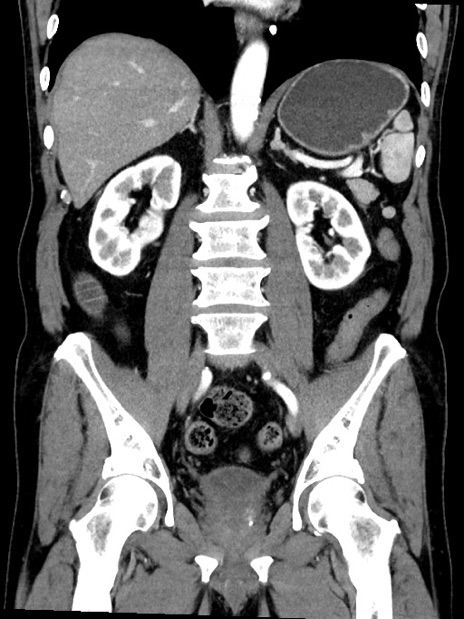

症例35(冠状断像)

【症例】70歳代 男性

【主訴】腹部膨満、嘔吐

【現病歴】昨日より腹部膨満感出現。本日増悪し、仙痛出現。嘔吐あり、受診。

【既往歴】糖尿病、胆摘後

【身体所見】BP 149/80mmHg、HR 74/min、BT 35.9℃、腹部:膨満、軟、圧痛なし。腸雑音減弱あり。上腹部正中切開瘢痕あり。

【データ】WBC 13500、CRP 1.72